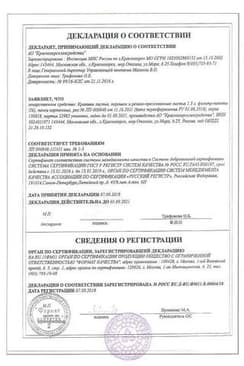

Сертификаты